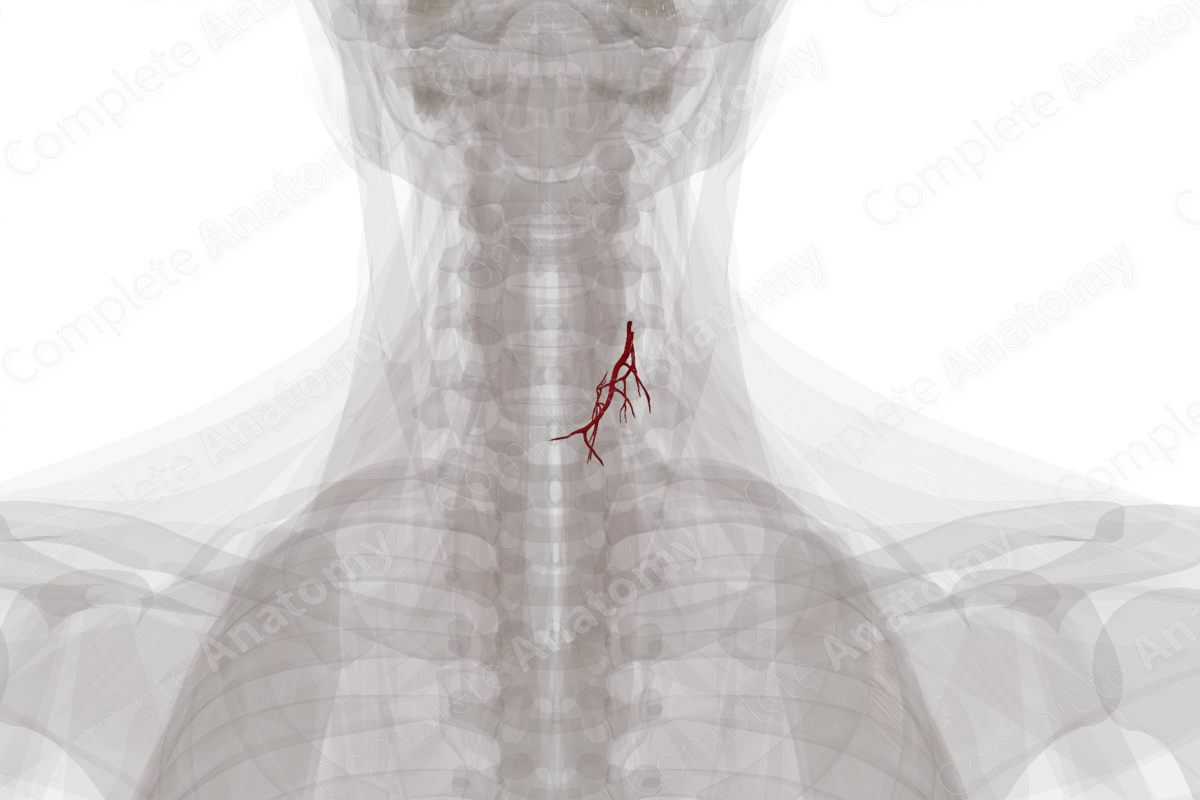

The thyroid gland receives a rich blood supply from branches of the superior and inferior thyroid arteries, and sometimes, by the thyroidea ima artery. These arteries form dense anastomoses on the surface or within the gland.